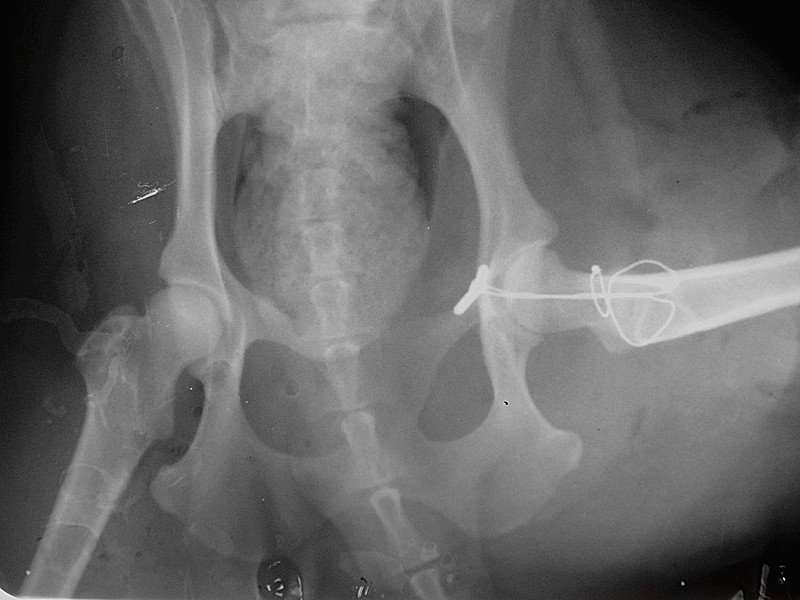

动物医学影像室:

动物医学影像室扬州大学动物医院影像室成立于2013年,由超声影像室和X线诊断室组成。该科室拥有数字化计算机X线诊断仪和彩色多普勒超声诊断仪,可进行大动物(马、牛)、小动物(犬、猫、兔子和龙猫等)及野生动物和海洋动物的影像诊断,为疾病…